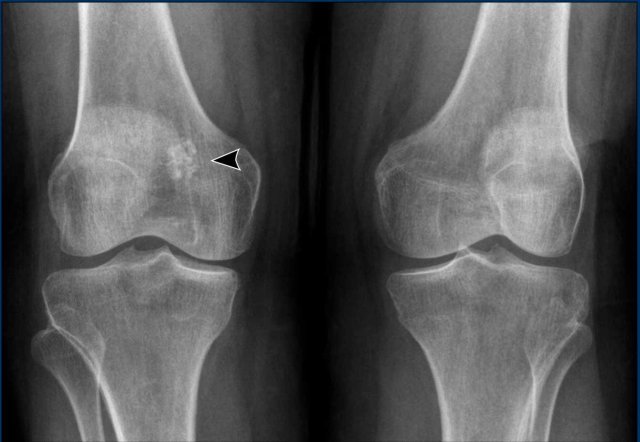

Images

The radiograph demonstrates an

osteolytic lesion in the distal femur containing typical popcorn calcifications

and showing anterior cortical scalloping (arrowhead).

On the sagittal MRI we can appreciate

that the tumor is larger than the area of calcifications on the radiograph,

measuring 8 cm.

The tumor is hyperintense on T2 STIR and contains multiple foci

of low signal intensity, corresponding to the chondroid matrix calcifications

on the radiograph.

Conclusion

Since there is no periosteal reaction or soft tissue mass, these findings fit with the diagnosis of ACT.

The patient remains in follow-up.